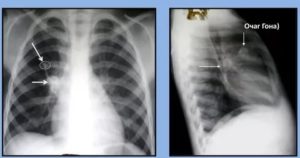

В повседневной жизни человек неоднократно сталкивается с возбудителем туберкулеза легких, даже не замечая этого. Подтверждением этому являются «случайные» находки при прохождении ежегодной плановой флюорографии, которые представляют собой очаги Гона. Как они формируются и несут ли опасность для организма, рассмотрим в этой статье.

Очаг Гона в легких является результатом первичного инфицирования человека микобактерией туберкулеза. Длительность его формирования в среднем составляет до 3 лет. Очаг Гона представляет собой овальное образование, иногда с неровными лучистыми контурами. Структура его представлена соединительной тканью, коллагеновыми волокнами, отложениями кальция. Размеры могут достигать 2 см.

Очаг Гона невозможно выявить при общем осмотре и лабораторных исследованиях. Единственные методы, позволяющие его диагностировать, – это рентгенологические.

К ним относятся:

- обзорная рентгенография органов грудной клетки в двух проекциях: прямой и боковой,

- компьютерная томография (КТ),

- магнитно-резонансная томография (МРТ).

При рентгенологических исследованиях очаг Гона представляет собой затемнение овальной (реже округлой) формы с резкими очертаниями, размерами до 5 мм. Образования могут быть единичными и множественными. Излюбленная их локализация – нижние и средние отделы легких. Иногда контуры очага могут быть неровные. Легочный рисунок неизменен, корень не расширен.

Выявление очага Гона на рентгенологических снимках не представляет трудностей. Однако ввиду отсутствия клинических проявлений, часто обнаруживается случайным образом.